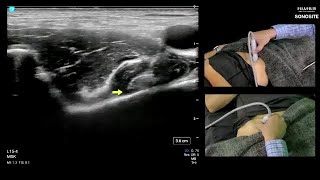

Examining Hip Anatomy and Structure with POCUS: Posterior Hip

December 18, 2020

Education

With Daniel Shelton, RT(R)

Watch now